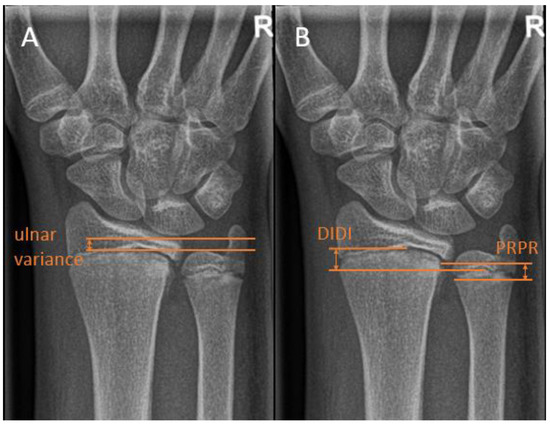

There are multiple ways of measuring the ulnar variance. In the method of perpendiculars, a line is drawn perpendicular to the longitudinal axis of the radius and through the most distal ulnar part of the radius. The distance between the adjacent distal cortical rim of the ulna relative to this line is then measured as the variance [17] (Figure 4A). In the method as described by Hafner et al. [18], a line is drawn perpendicular to the longitudinal axis of the ulna, touching the most proximal prominent point of the ulnar metaphysis on the radial side. Secondly, a line is drawn on the radius perpendicular to its longitudinal axis touching the most proximal point of the radial metaphysis on the ulnar side. Ulnar variance is then defined as the distance between these lines. In the literature, these distances are referred to as “Proximal–PRoximal distance [17]. Conversely, the variance can be measured using the distance of the most distal points of the radial and ulnar metaphysis. This method is referred to as “Distal–DIstal” distance. (Figure 4B).

Figure 4. Distal ulna radiographic reference lines. (A) The Hafner method for measuring ulnar variance. (B) The method of perpendiculars for measuring ulnar variance, with ‘PRPR termed as the two most proximal points of the physis and ‘DIDI’ termed as the two most distal points of the physis.